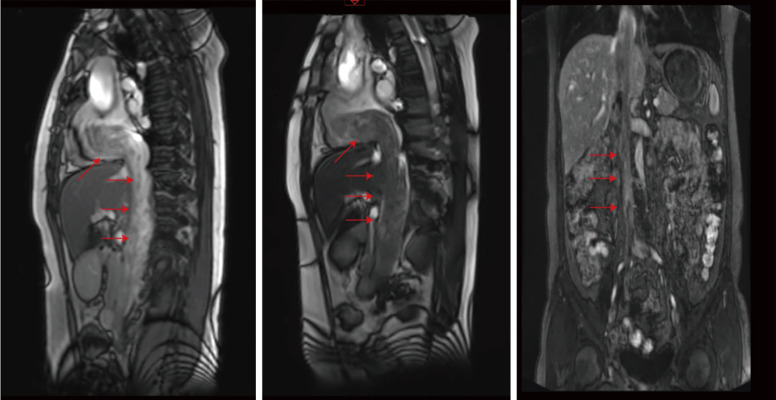

Case description: We report a case of retrogradely growing IVL, originating in the uterus and extending along the venous system to the right heart. At the same time, this leiomyomatosis retrogrades into the right external iliac vein. A 48-year-old woman with a mass in the IVC was admitted to Wuhan Union Hospital. She had undergone a hysterectomy for fibroids 2 years previously. Computed tomography venography and three-dimensional reconstruction revealed filling defects in the IVC, right internal and external iliac veins, right common iliac vein, right renal vein, and right atrium. After a multidisciplinary consultation, IVC leiomyomatosis was considered, and surgical treatment was performed.

Conclusions: We report a case of retrogradely growing IVL. It originates in the uterus, extends along the venous system to the right internal iliac vein, and grows retrogradely into the external iliac vein. This is a new growth path that has rarely been mentioned.